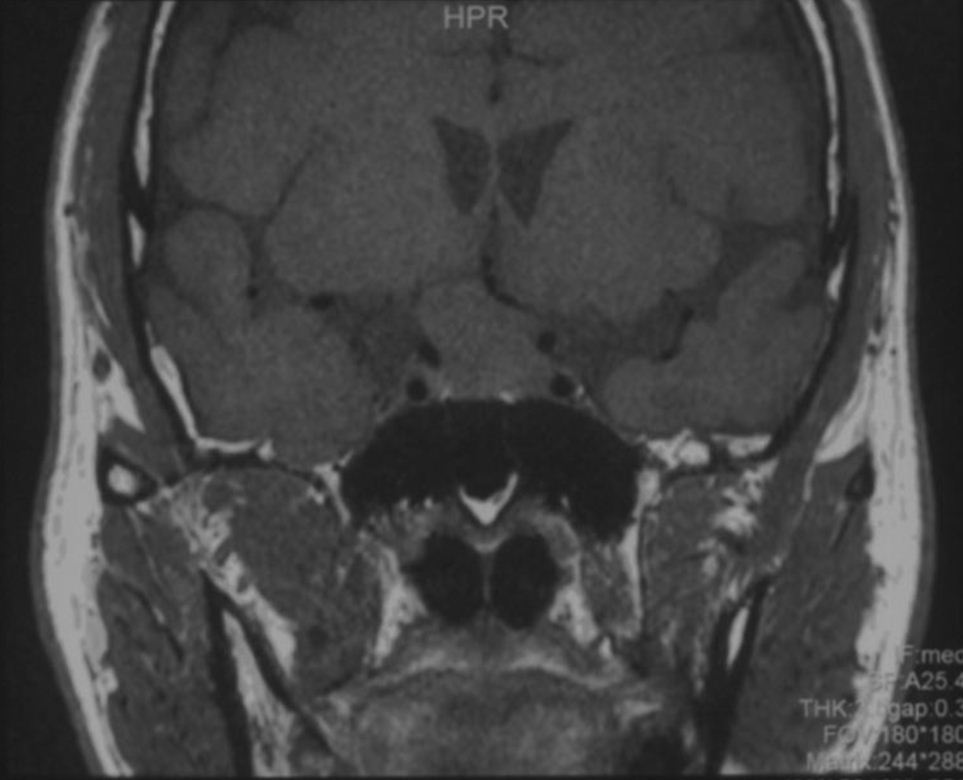

术后即刻CT示:

术区干净,肿瘤切除满意。